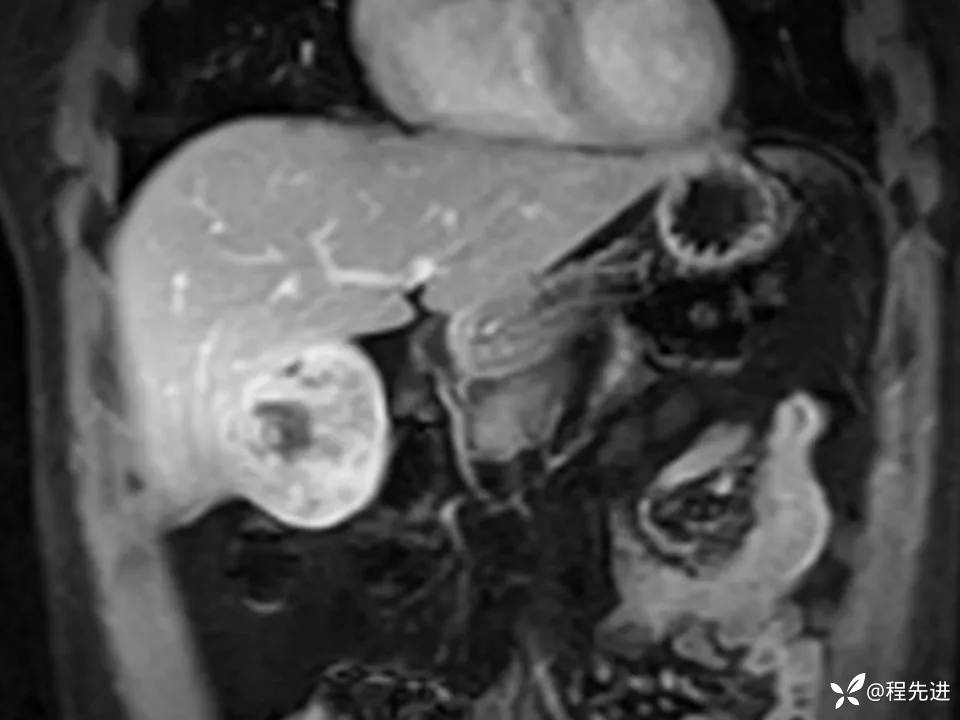

患者性别:男

患者年龄:27岁

简要病史:体检发现肝脏占位2周

既往史:平素体健,无特殊

实验室检查:(-)